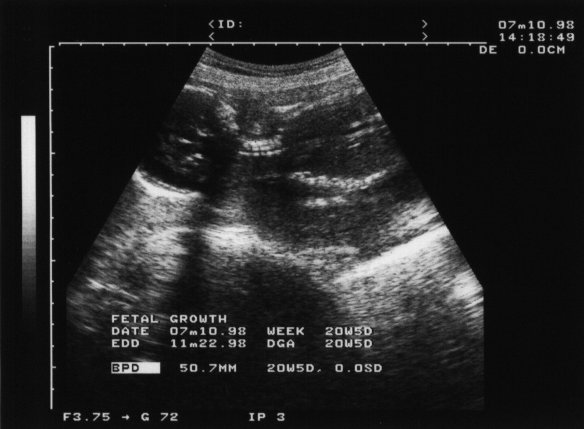

98年7月10日(妊娠20週4日)

ついに「エコー」には入りきらない体長まで成長してしまった. この頃の成長率(膨張率?)って,信じられない勢いだ.

しっかり頭も分るし,首の骨も写ってる. 心臓から出る動脈も形成されているそうな.(動画だったらもっと分りやすかったかも知れないけど,私もまだ見たことがない.)